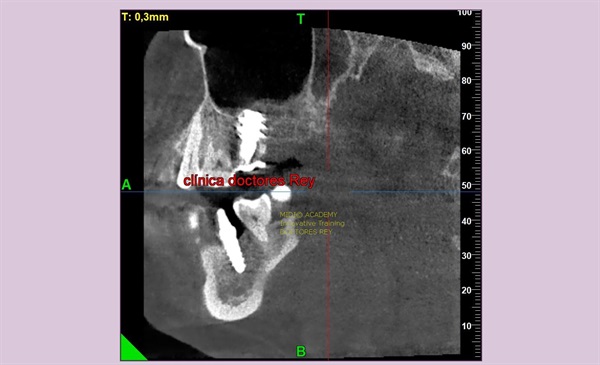

2-Implantes monobloque, en maxilar inferior. MIDI® TECHNIQUE® -US.

4x11,5. colocados con técnica ultarasónica MIDI®, hueso de calidad baja.

1- Implante de 9 mm de diámetro en maxilar superior post extracción + PRF. MIDI® TECHNIQUE®, no drill.

IMPLANTE EN MAXILAR SUPERIOR post extracción de diametro amplio 9 mm.

1- Implante de 9 mm de diámetro en maxilar superior post extracción + PRF. MIDI ®TECHNIQUE®, no drill.